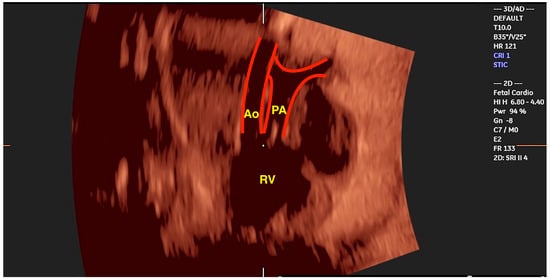

2.2. Transposition of the Great Arteries (TGA)

- Shih, J.C.; Shyu, M.K.; Su, Y.N.; Chiang, Y.C.; Lin, C.H.; Lee, C.N. ‘Big-eyed frog’ sign on spatiotemporal image correlation (STIC) in the antenatal diagnosis of transposition of the great arteries. Ultrasound Obstet. Gynecol. 2008, 32, 762–768. [Google Scholar] [CrossRef]

- Araujo Júnior, E.; Tonni, G.; Bravo-Valenzuela, N.J.; Da Silva Costa, F.; Meagher, S. Assessment of Fetal Congenital Heart Diseases by 4-Dimensional Ultrasound Using Spatiotemporal Image Correlation: Pictorial Review. Ultrasound Q. 2018, 34, 11–17. [Google Scholar] [CrossRef] [PubMed]